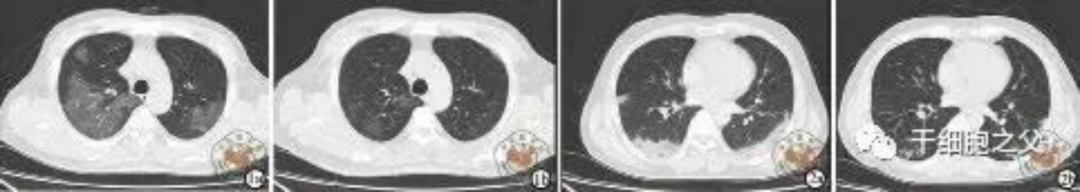

如圖所示,1a-1b:細胞輸注后,炎癥指標改善,復查胸部CT提示雙肺病灶較前吸收,呼吸道癥狀改善,新型冠狀病毒核酸檢測連續2次陰性,治愈出院。圖2a-2b:2次干細胞輸注后炎癥指標改善,復查時氧合指數升高至301 mmHg,胸部CT提示雙肺病灶較前吸收,患者呼吸道癥狀改善,新型冠狀病毒核酸檢測連續2次陰性,治愈出院。